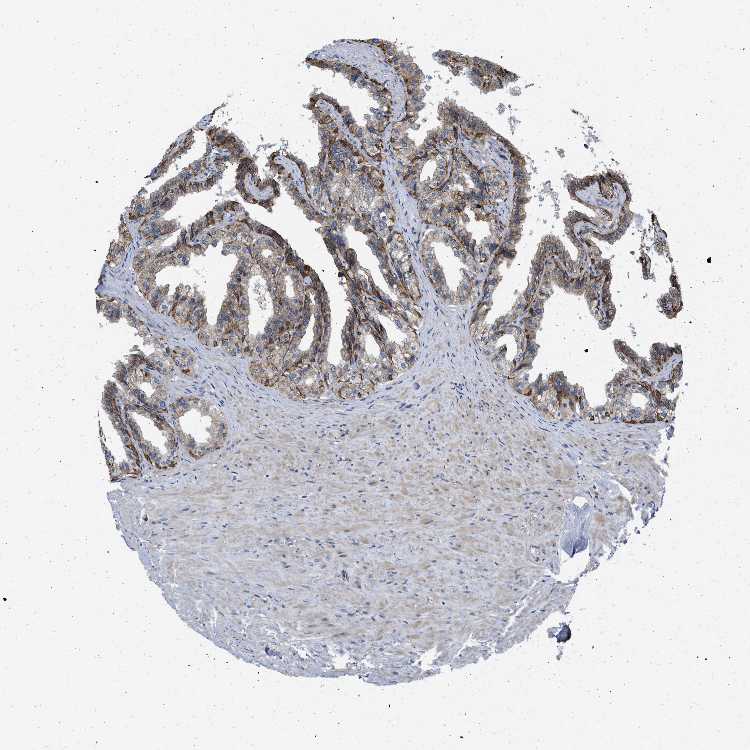

SEMINAL VESICLE - Antibody stainingi

Antibody staining in the annotated cell types in the current human tissue is reported as not detected, low, medium, or high, based on conventional immunohistochemistry profiling in selected tissues. This score is based on the combination of the staining intensity and fraction of stained cells.

Each image is clickable and will lead to virtual microscopy that enables deeper exploration of all samples and also displays staining intensity scores, fraction scores and subcellular localization as well as patient and tissue information for each sample.

Antibody HPA013397

Glandular cells High